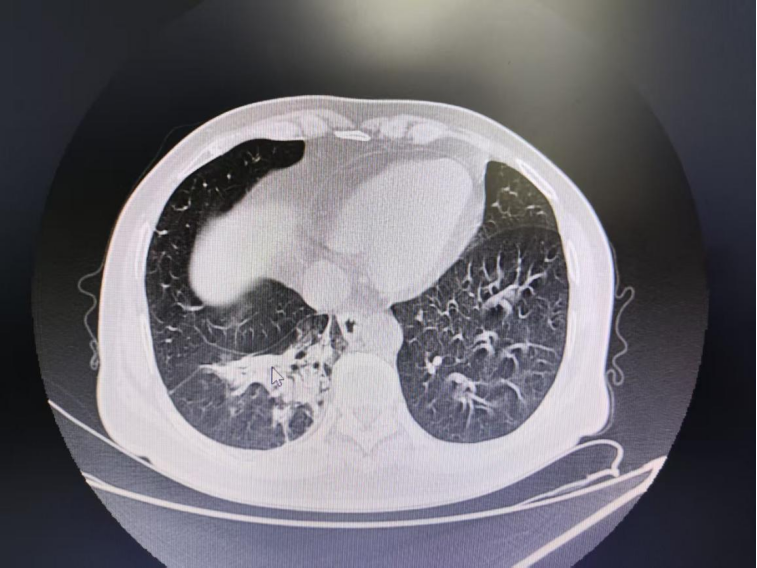

近日,市一医院经开区院区呼吸内科收住一患者。他因反复咳嗽半月余伴高热,在社区医院治疗一周无效后入院。入院时血糖高达29.2mmol/L,虽经抗感染、抗炎、止咳、降糖等常规治疗,咳嗽仍无明显缓解。胸部CT提示阻塞性肺炎,呼吸内科副主任医师章秀高度怀疑气道异物。与患者及家属充分沟通后,行支气管镜下查病因,成功取出一枚黄豆。术后患者咳嗽症状明显改善。追问病史,患者方忆起发病初期确有吃黄豆零食时一口闷下、发生呛咳的经历,因平素反复呼吸道感染,故未予重视。